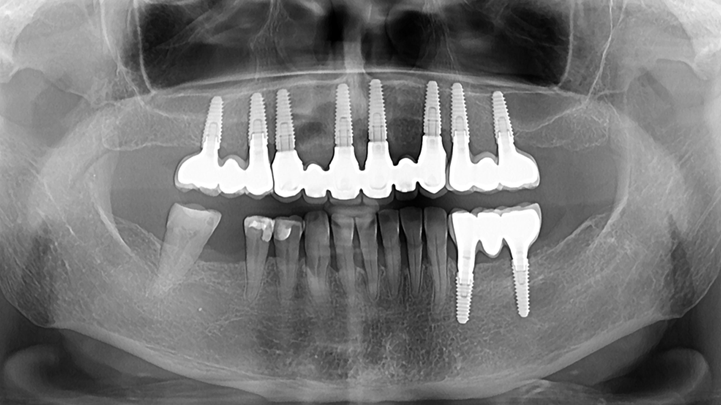

Clinical case: Advantage of fuse abutment with AnyRidge implant for immediate loading in

upper fully edentulous case

- Courtesy of Dr. Kwang Bum Park -

“AnyRidge shows excellent initial stability

& stable results after immediate loading in

upper fully edentulous case. ”

Clinical case: Extraction of all teeth in upper maxilla,

immediate implant placement, & provisionalization

- Courtesy of Dr. Iulian Filipov, Romania -